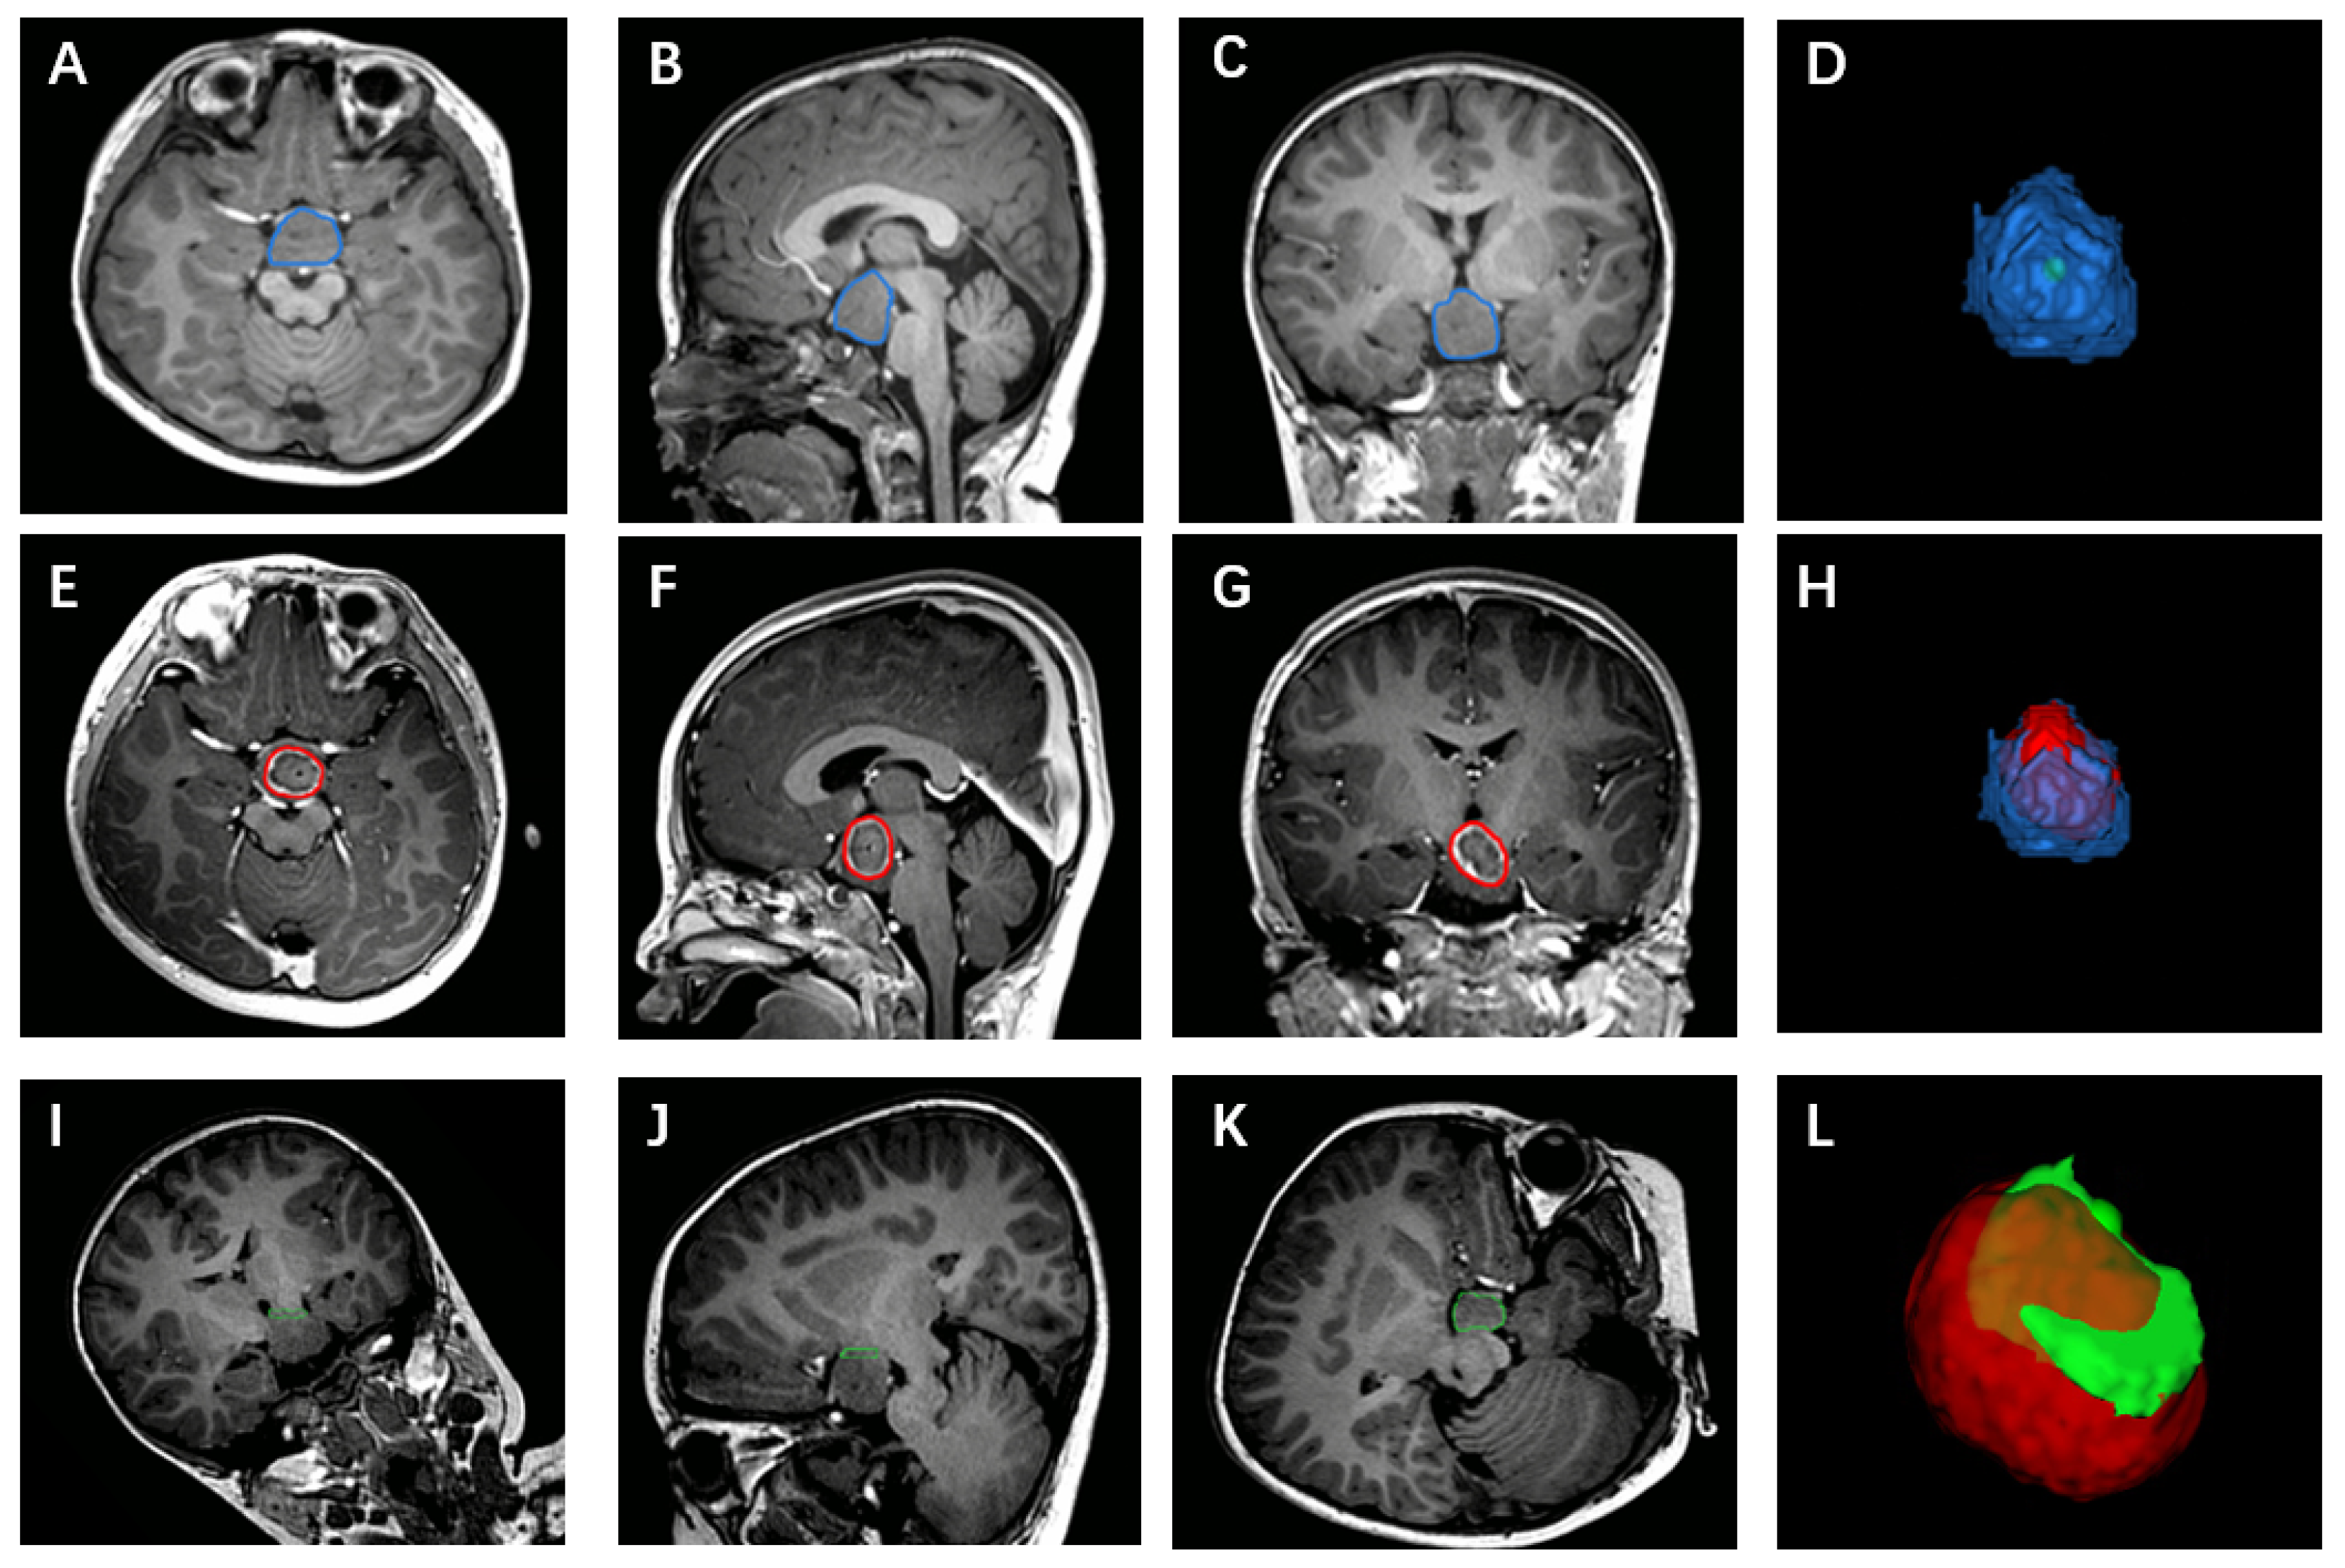

2.2. Surgical Procedure